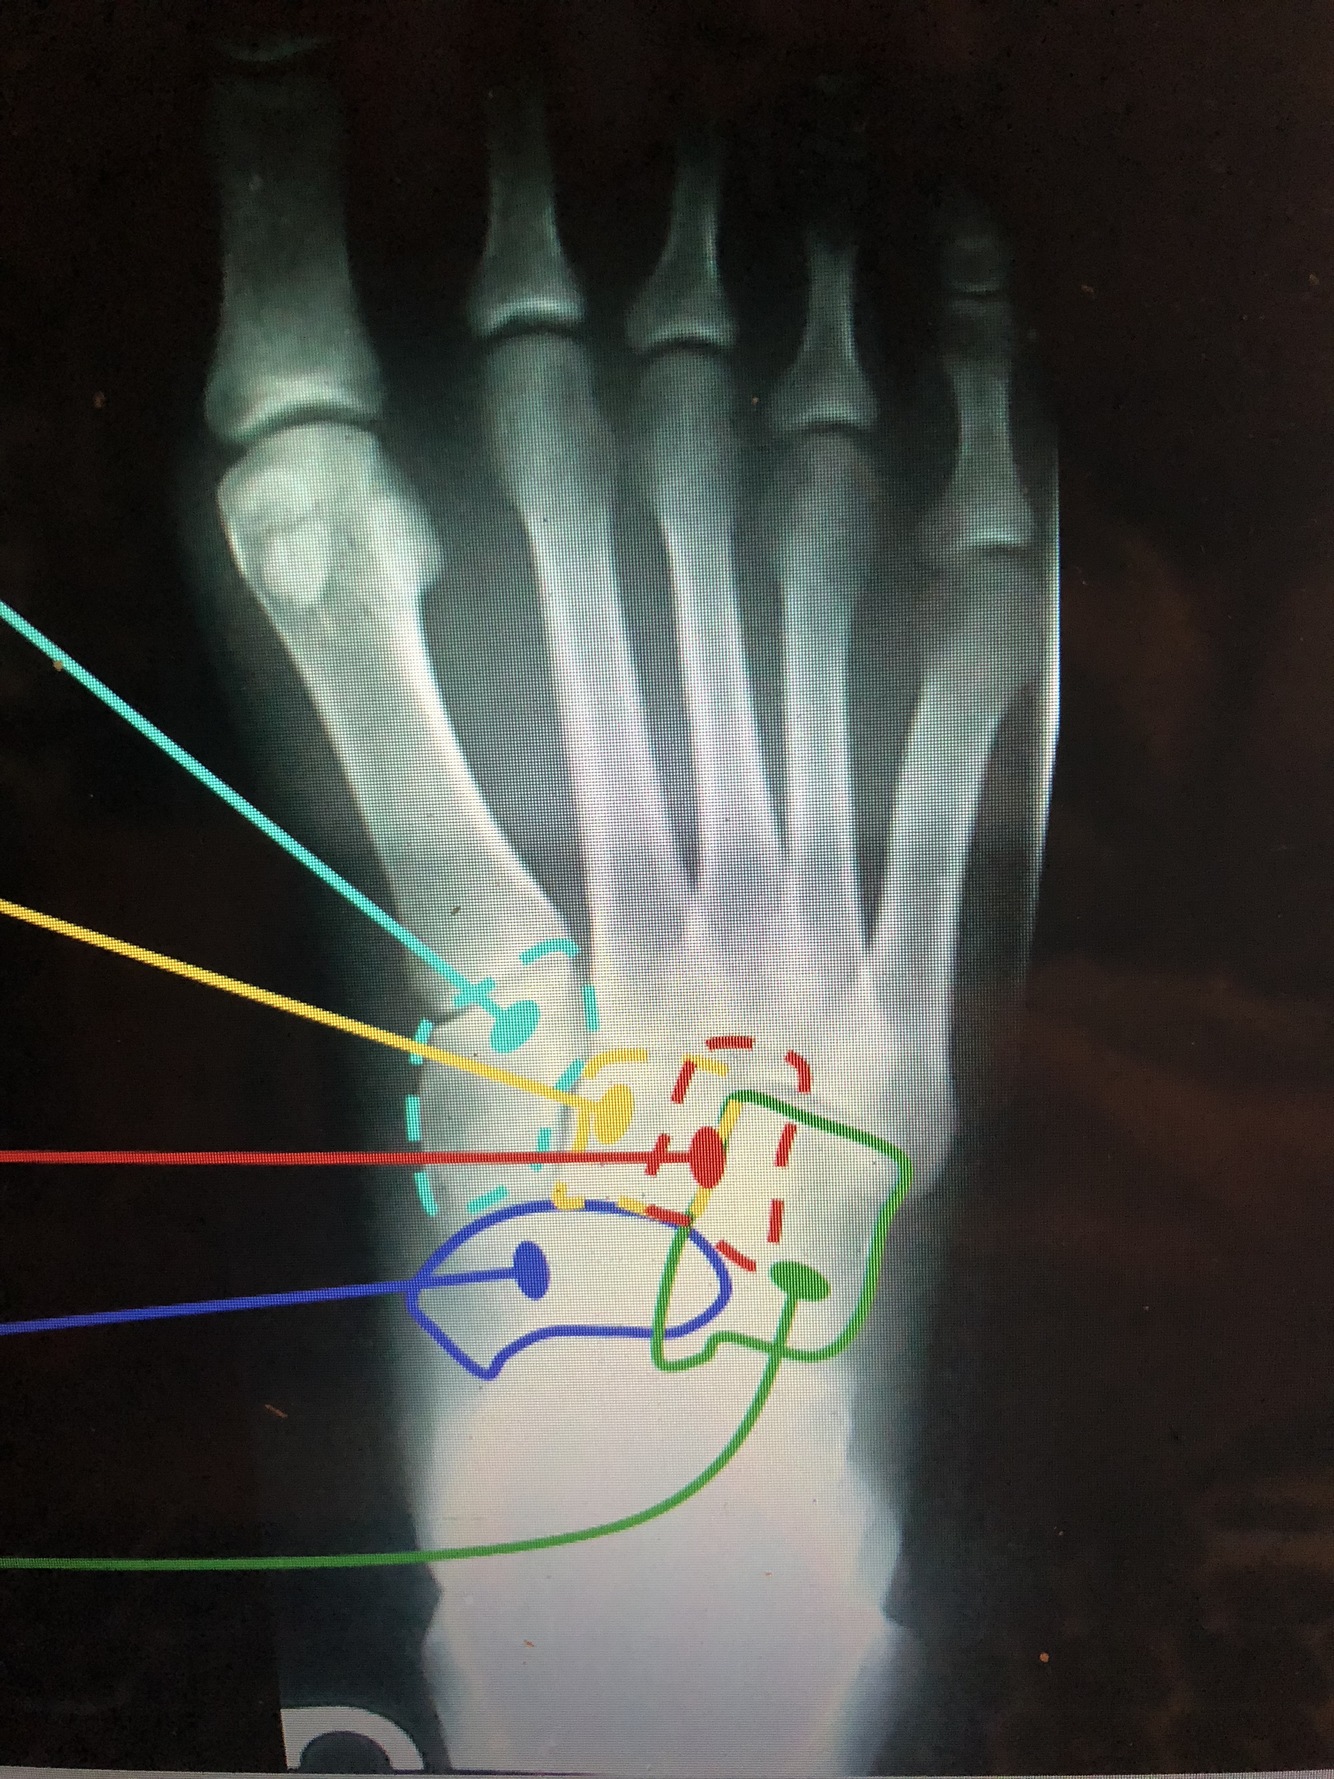

What bone is light blue?

Medial Cuneiform (1st)

What bone is yellow?

Intermediate Cuneiform (2nd)

What bone is red?

Lateral Cuneiform (3rd)

What bone is blue?

Navicular

What bone is green?

Cuboid

What is the red line?

head of 1st metatarsal

What is the dark blue line?

Neck of 2nd metatarsal

What is the yellow line?

Shaft of 3rd metatarsal

What is the light blue line?

base of the 3rd metatarsal

Styloid Process of the 5th Metatarsal

• Common fracture site in an inversion ankle sprain due to the pull of the peroneus brevis muscle